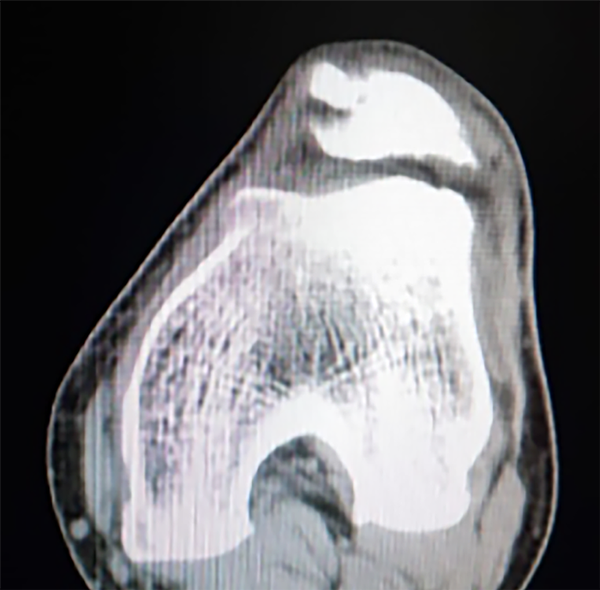

Dado el antecedente quirúrgico, se solicitaron nuevos estudios complementarios en los que se observó una tróclea plana (Dejour C) en TC y radiográficos (figs. 2 y 3). Se decidió realizar revisión de plástica del LPFM con tendón cuadricipital + trocleoplastia con técnica de profundización del sulcus.

Figura 2: TC. Obsérvese secuela de antecedente quirúrgico patelar (plástica de LPFM).